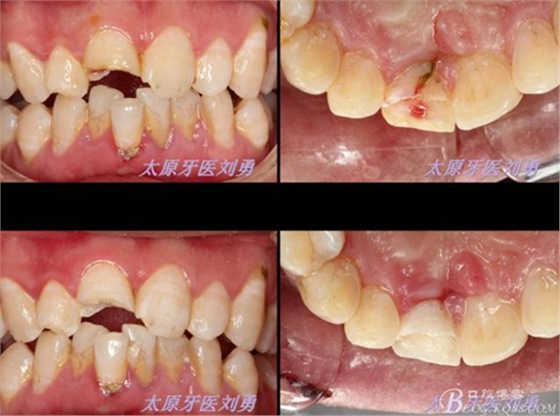

另外一例為本人高中同學(xué),同樣不慎摔倒,導(dǎo)致A1折裂,露髓,且舌側(cè)有一碎片折裂至齦下3mm左右,先看術(shù)前圖片:

首先為了粘結(jié)斷端,選擇去除牙髓,行一次性根管治療后,首先處理舌側(cè)碎片,圖中可見(jiàn)舌側(cè)碎片裂至齦下,且牙齦有明顯撕裂,如果拔除折裂片,則難以修復(fù),或者選擇牙冠延長(zhǎng)或者選擇即刻種植,本人做了一種嘗試:粘結(jié)舌側(cè)碎片,首先對(duì)位碎片,發(fā)現(xiàn)對(duì)位后非常密合,如果采用全酸蝕粘結(jié)手段,則務(wù)必要掀開(kāi)碎片,則有可能導(dǎo)致出血污染粘結(jié)面,導(dǎo)致粘結(jié)失敗。于是小心謹(jǐn)慎輕微掀開(kāi)碎片,無(wú)滲血,用最小號(hào)毛刷蘸入自酸蝕粘結(jié)劑,然后直接復(fù)位碎片,并且壓緊,讓粘結(jié)劑能均勻擴(kuò)散至斷面深處,光固化。術(shù)畢檢查,碎片粘結(jié)完好。如下圖:

因周末處理該患者,無(wú)法領(lǐng)取纖維樁,于是將切斷的碎片復(fù)位后,從碎片舌側(cè)面制備一隧道直至根管口深處,(想法是注入流體樹(shù)脂形成一個(gè)樹(shù)脂樁加強(qiáng)固位),然后同上病例中所用方法,粘結(jié)固定斷端。如下圖: